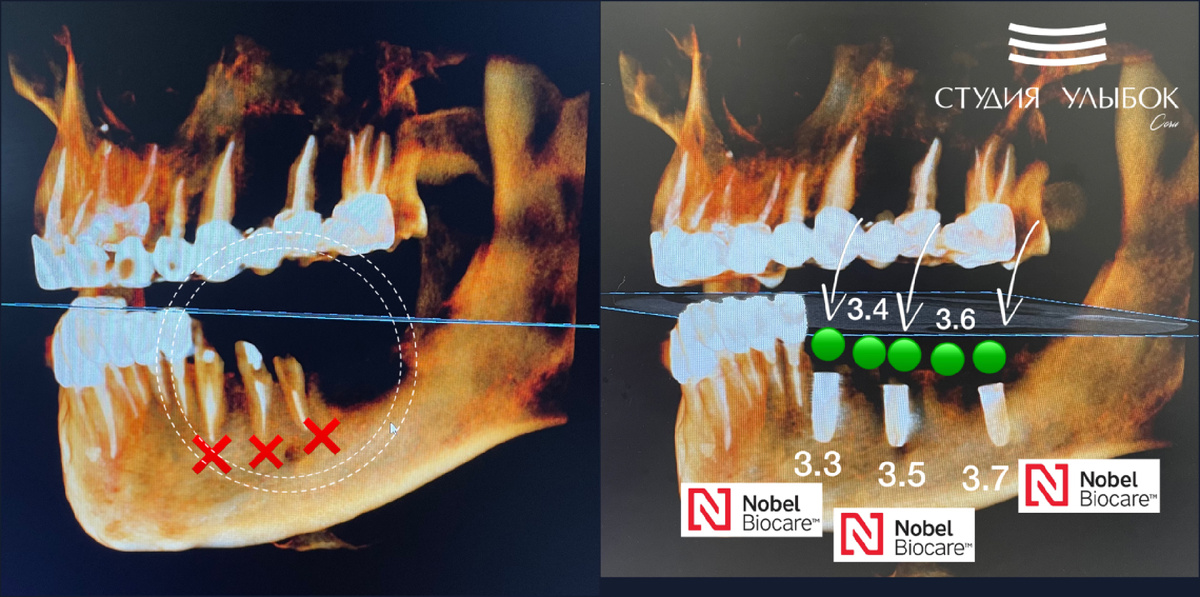

Кейс детальной имплантации. Пациент обратился с жалобой на перелом мостовидной конструкции снизу слева. Это протезирование 4-х летней давности, которое было произведено в другой клинике. После проведения диагностики и КЛКТ исследования мы увидели, что произошел перелом зубов: 33, 34, 35. Детальная имплантация Nobel (Швеция) была спланирована в цифровом протоколе и проводилась с помощью хирургического навигационного шаблона. Имплантаты были установлены по месту: 33, 35, 37. Зубы, которые расположены между установленными имплантами, 34 и 36, будут мостом будущей конструкции, которая будет иметь 3 опоры (это имплантаты) и 5 зубов (коронок). Операция по установке 3-х имплантатов Nobel Beocare была проведена очень точно и весьма успешно. Мы получили хорошую первичную стабильность. Дальнейший этап по протезированию, т.е. установки коронок на имплантаты спланирован по прохождению 3-х месяцев. Работа врача стоматолога-хирурга-имплантолога, Григория Эдуардовича Марванова. #имплантантынобель #с

Кейс детальной имплантации. Пациент обратился с жалобой на перелом мостовидной конструкции снизу слева. Это протезирование 4-х летней давности, которое было произведено в другой клинике.

После проведения диагностики и КЛКТ исследования мы увидели, что произошел перелом зубов: 33, 34, 35.

Детальная имплантация Nobel (Швеция) была спланирована в цифровом протоколе и проводилась с помощью хирургического навигационного шаблона. Имплантаты были установлены по месту: 33, 35, 37. Зубы, которые расположены между установленными имплантами, 34 и 36, будут мостом будущей конструкции, которая будет иметь 3 опоры (это имплантаты) и 5 зубов (коронок).

Операция по установке 3-х имплантатов Nobel Beocare была проведена очень точно и весьма успешно. Мы получили хорошую первичную стабильность. Дальнейший этап по протезированию, т.е. установки коронок на имплантаты спланирован по прохождению 3-х месяцев.